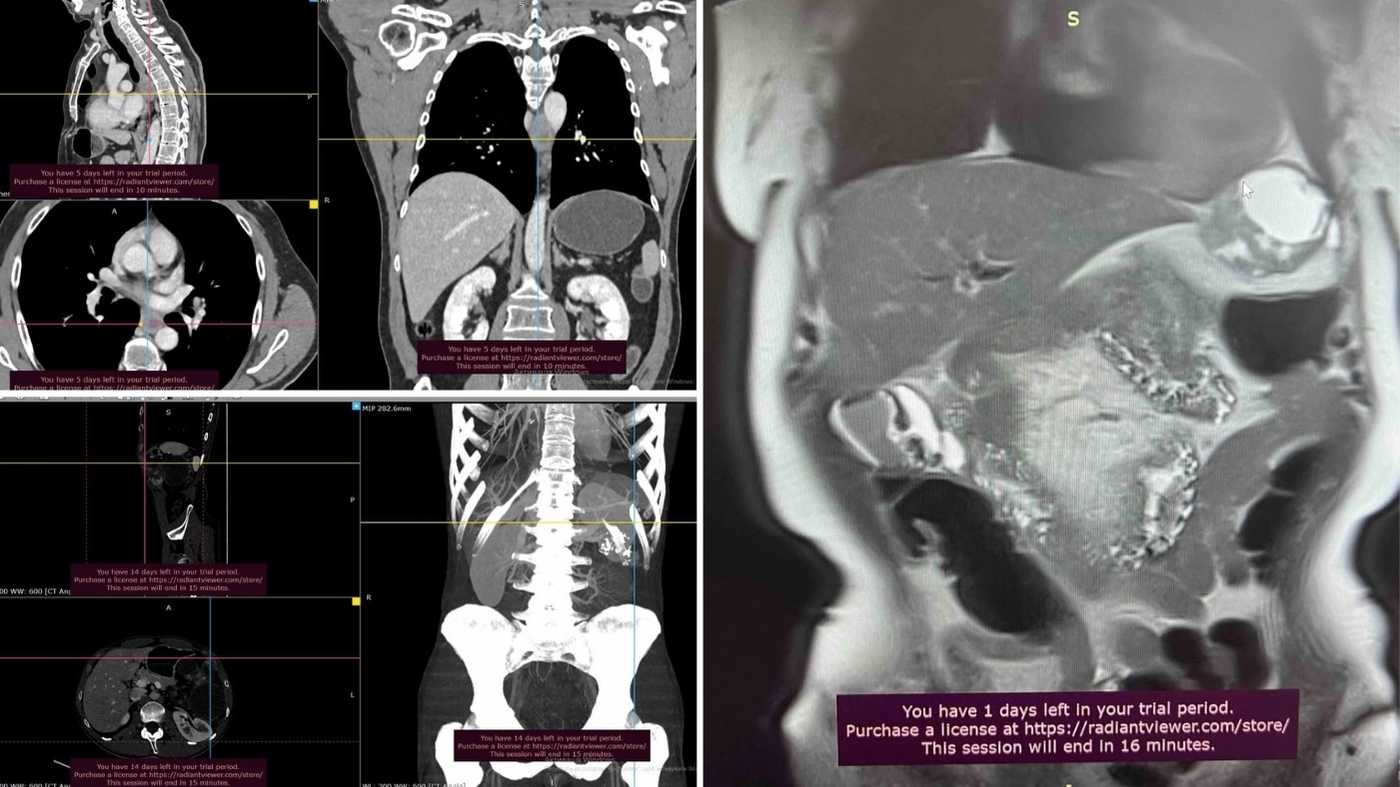

- злоякісна пухлина діафрагми, що поширювалась на стінку серцевої сумки (перикарда)

- стромальна гастроінтестинальна пухлина середньої третини стравоходу, яка викликала порушення ковтання та розташовувалась у складній анатомічній зоні — між стравоходом і низхідною аортою

- тератома великих розмірів лівого піддіафрагмального простору у молодого пацієнта, яку спостерігали понад три роки. Пухлина призвела до зміщення прилеглих анатомічних структур.